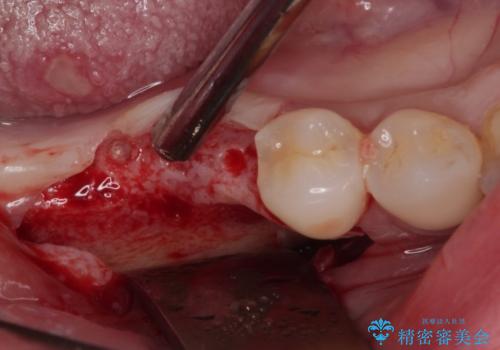

歯の周りの炎症が顕著であったため、抜歯後炎症が治まるのを待ち、咬み合わせが改善できる位置にインプラントを埋入することとしました。

長年の咬合により、周囲の奥歯がすり減っているため、よりインプラントが長い期間安定するよう、睡眠時にはマウスピースを装着することを強く推奨しています。

- 外科手術のため、術後に痛みや腫れ、違和感を伴います